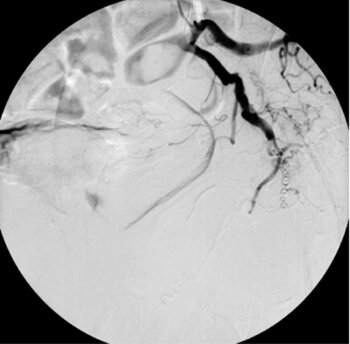

Digitale Subtraktionsangiografie: Wegen wiederkehrenden Blutungen aus einem Scheidentumor erfolgte die Sondierung zunächst der linken A. pudenda (tumorversorgendes Gefäß).

Digitale Subtraktionsangiografie: Sodann wurde die linke A. pudenda mit Spiralen embolisiert (verschlossen)

Digitale Subtraktionsangiografie: Dasselbe Prozedere erfolgte auf der Gegenseite, mit Sondierung der rechten A. pudenda

Digitale Subtraktionsangiografie: Spiralembolisation dieses Gefäßes. Die Kontrolle zeigt wie auf der Gegenseite einen kompletten Verschluss. Die Blutungen der Patientin kamen hiernach zum Stillstand.